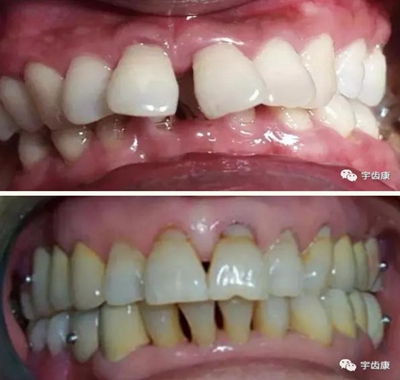

保護(hù)牙體組織

基牙具有良好的固位形

基牙具有良好的抗力形

預(yù)留修復(fù)體的空間

邊緣的適合性

保護(hù)牙周組織

6. 保護(hù)牙周組織

牙體預(yù)備時需注意的問題

模型檢查

模擬預(yù)備